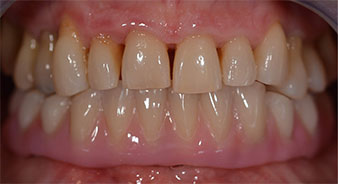

The impression and bite registration were then performed so that the dental technician could begin producing the provisional restoration immediately. This was then screwed in on the same day (Fig. 17 and 18).

Implants

Fig. 17

Fig. 18